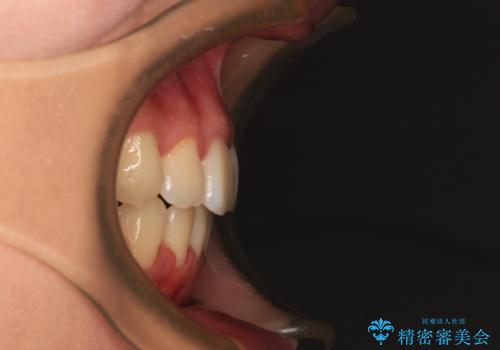

舌の突出癖によるオープンバイトになっていたため、インビザラインによるマウスピース矯正をおすすめしましたが、自己管理の自信がないとのことで、ワイヤー装置による矯正治療を行うこととしました。

舌の突出癖が認められると、上下前歯の隙間を閉じることができません。

舌のトレーニングをしっかりと行っていただくことで、歯列を整えることができます。